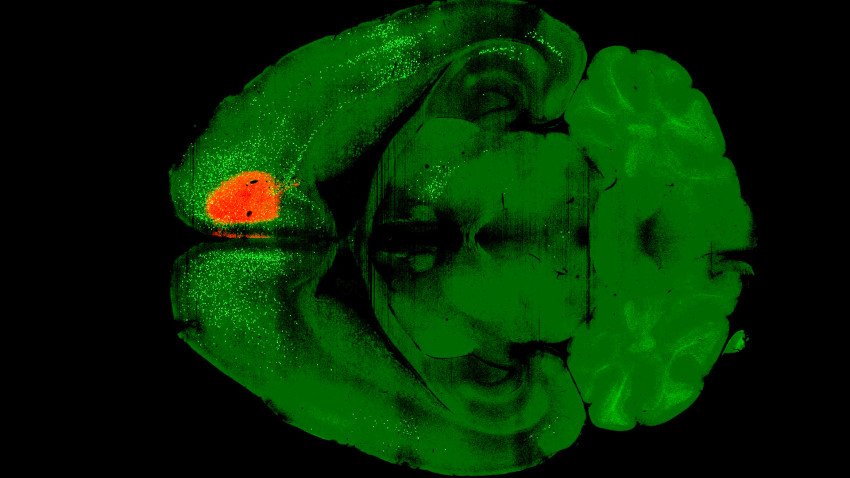

The study involved administering a single dose of psilocybin to the frontal cortical pyramidal neurons of mice. One day later, the researchers introduced the modified rabies virus, which labels neurons connected to those affected by psilocybin. After a week, the team imaged the brain and compared its connectivity to that of a control group that received only the virus. The results indicated that psilocybin significantly weakened recurrent connections within the cortex, which may elucidate why individuals with depression often engage in rumination, or persistent negative thinking.

The research team, led by Alex Kwan, Ph.D., a professor of biomedical engineering at Cornell University, adopted a novel approach to investigate how psilocybin alters brain connectivity. Rather than solely relying on optical imaging, the team introduced a variant of the rabies virus, engineered by collaborators at the Allen Institute for Brain Science in Seattle. This virus acts like a mapping tool, tracing the intricate wiring of the brain and revealing how psilocybin adds new connections.